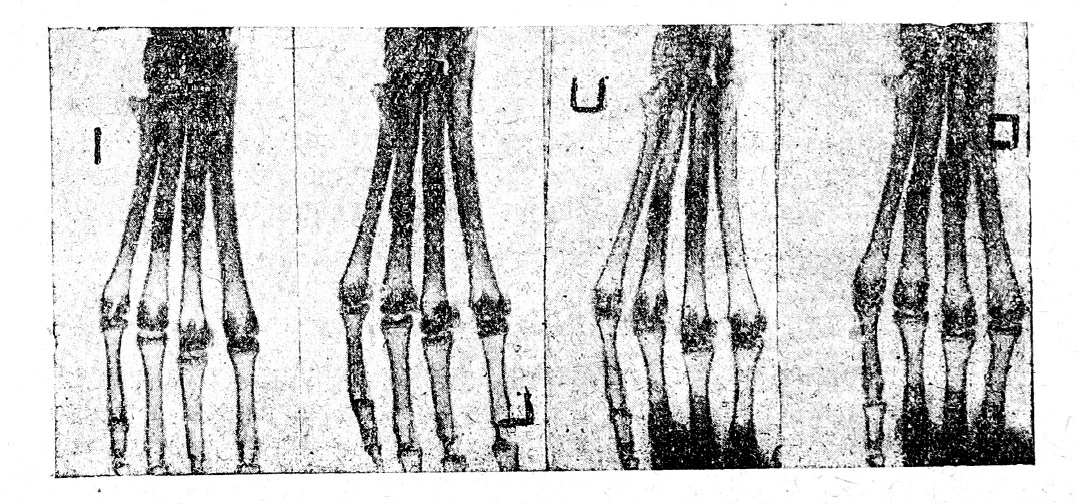

При сравнительной оценке результатов, полученных в опытах других серий, я учитываю степень прочности сращения, кости по интенсивности отложения солей в костной мозоли, а также по характеру ее формирования на основании изучения рентген-картины не только к моменту окончания опыта, но и в остальные более ранние сроки. Ввиду этого я позволю себе привести рентгенограммы, полученные на 15, 20 и 25 день в опыте № 23, как наиболее характерном для данной серии (рис. №№ 1—4). На этих рентгенограммах заметно, что на 15-й день образовалась едва видимая тень от костной мозоли, в последующие дни процесс ее оссификации идет медленно и на 30-й день еще нет полного обизвествления костной мозоли, в результате чего еще ясно видна щель на месте перелома на третьей} плюсневой кости.

Рис. 1—4. Контрольный перелом. Сращение полное произошло на 30-й день. Опыт № 23.

Опыты этой контрольной серии показали, что сломанные кости у кроликов срастаются обычно в 30 дней; однако, к этому сроку у них еще не заканчивается процесс интенсивного отложения солей в костной мозоли, так как на рентгенограммах еще не обнаруживается их мощного отложения.